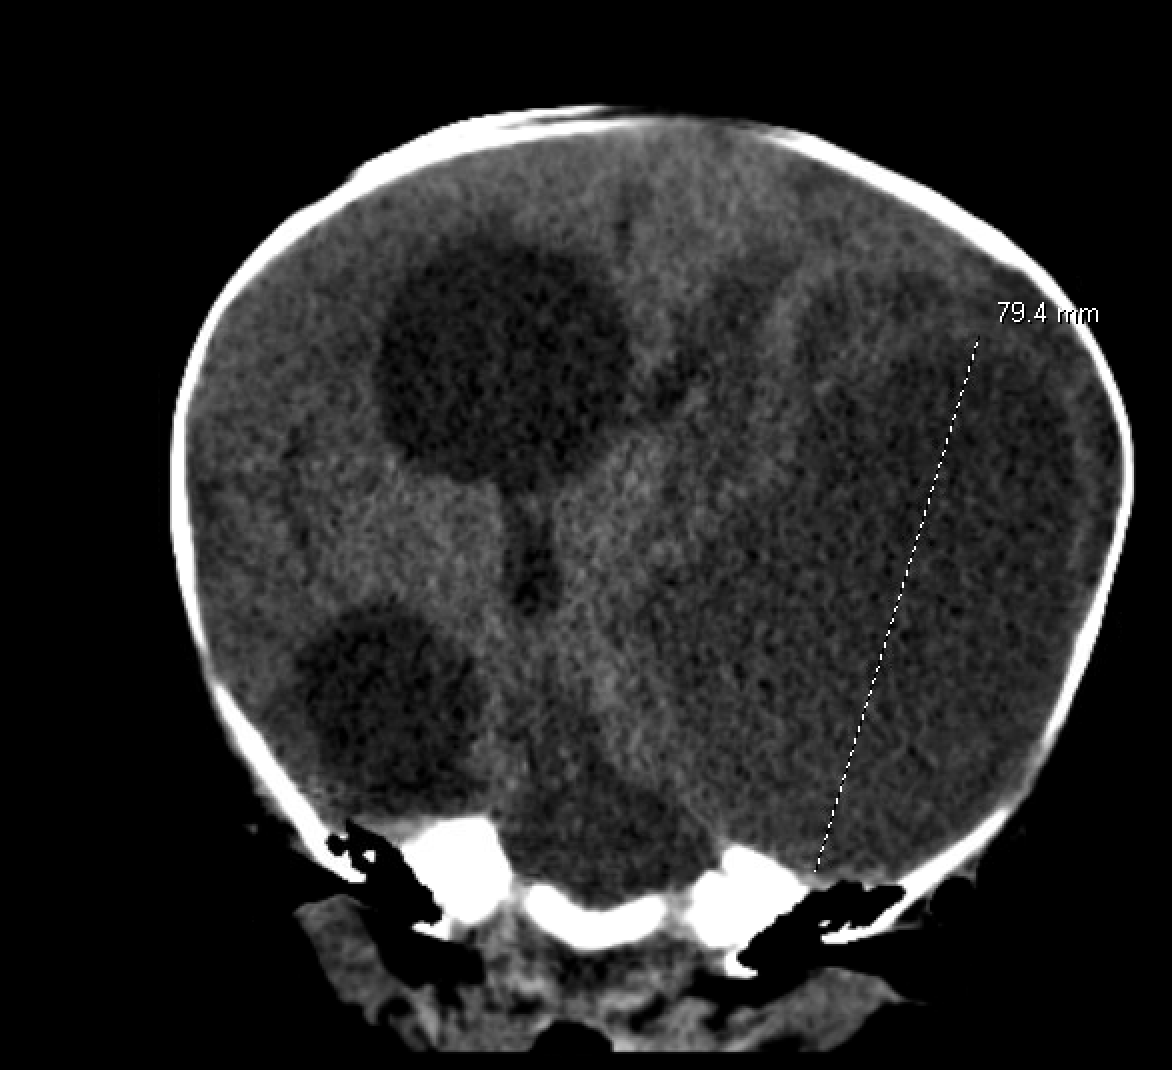

Laboratory evaluation was significant for a sodium of 128, potassium of 4.3, and creatinine 0.20. CBC was significant for a white blood cell count 19.0, hemoglobin 8.5, and platelets 1,086. Computed tomography of head without contrast demonstrated a large left-sided intracranial abscess with marked enlargement of the right lateral and third ventricles, concerning for obstructive hydrocephalus (Figure 2).

Figure 2